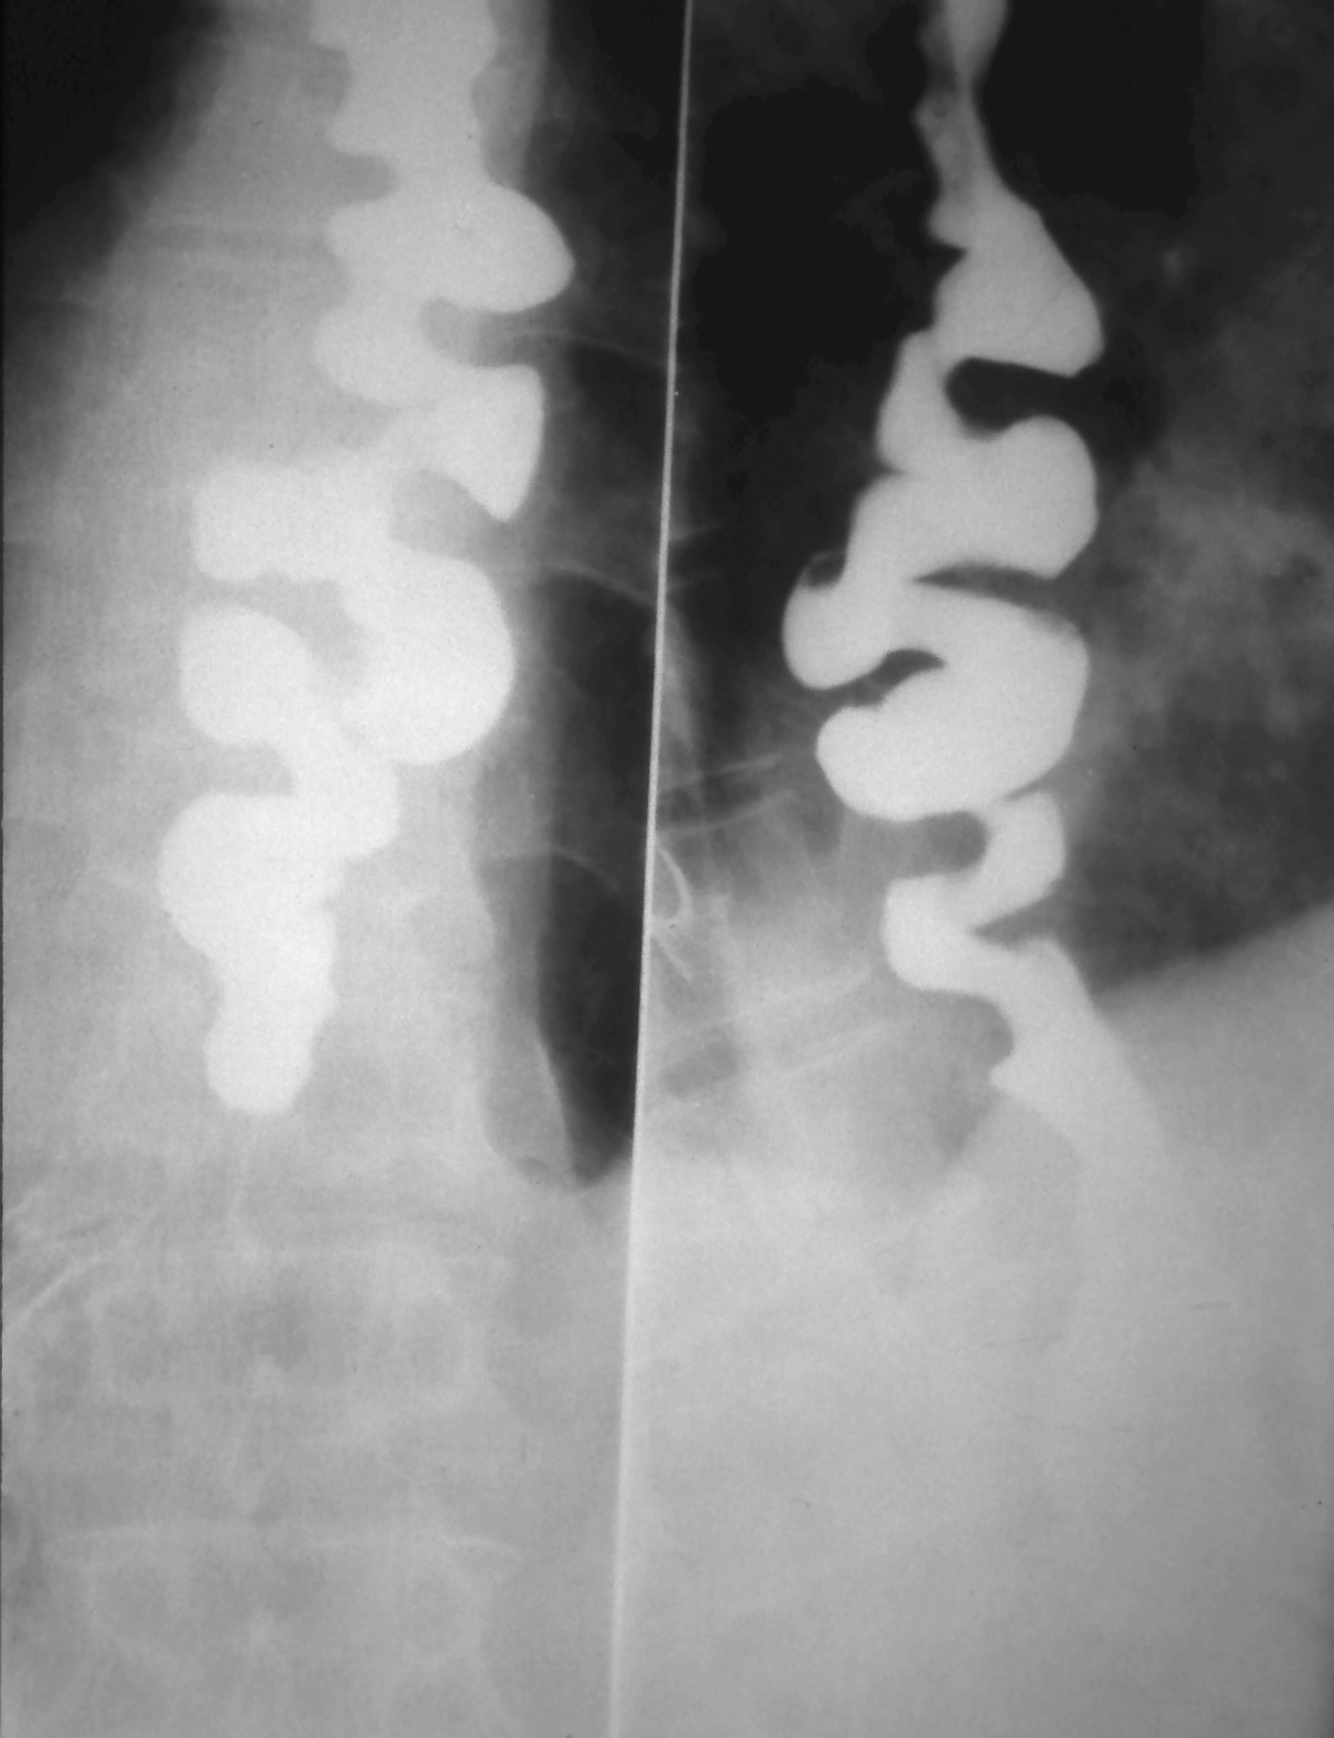

How would you investigate and manage Achalasia?

Investigations

How would you investigate and manage diffuse oesophageal spasm?